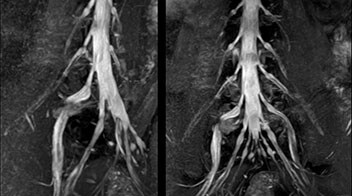

“NerveVIEW can clearly show nerve courses and presence of nerve compression. However, when multiple abnormalities are seen, it can still be hard to determine which nerve is causing the symptoms,” says Dr. Yabuki. “In our experience so far, we see abnormal findings on NerveVIEW in about 70% of elderly patients. As the pain is usually caused by only one nerve, we thus need to find the exact corresponding nerve.” “With a nerve root block, the patient's pain is improved by infiltration of local anesthesia directly around the nerve root considered to be responsible. Knowing such nerve root block findings prior to image interpretation, helps to easily recognize abnormal findings on NerveVIEW as well. In other words, without a priori knowledge, based on symptoms and/or nerve root block findings, we must be aware of the possibility of overdiagnosis.”

The addition of the nerve-selective NerveVIEW sequence to its spine MRI protocol has given NFMC competitive advantages, according to Tanji. “Since we started including NerveVIEW routinely, the demand for lumbar spine MRI examinations has increased, especially for pre-surgical planning purposes and for patients with chronic lower extremity symptoms,” he says. “Moreover, because no other hospitals in our region are doing nerve plexus imaging yet, we often receive referrals for MR neurography studies from other hospitals even if they have an MRI scanner. Some requests come from as far as 100 km away. NerveVIEW definitely provides us a competitive advantage.” “Based on our experience, we can certainly recommend NerveVIEW to other centers,” Dr. Yabuki adds. “The sequence opens up many possibilities to facilitate the diagnosis of lower extremity pain and to inform our decision-making regarding therapy and surgery.”

“NerveVIEW is really useful for those cases where a nerve disorder is strongly suspected based on the clinical examination but our regular MRI images do not show any findings. These atypical herniations and spinal canal stenosis, occurring in 5% to 15% of the total lumbar herniation/stenosis cases are our main target when using NerveVIEW,” says Dr. Yabuki.